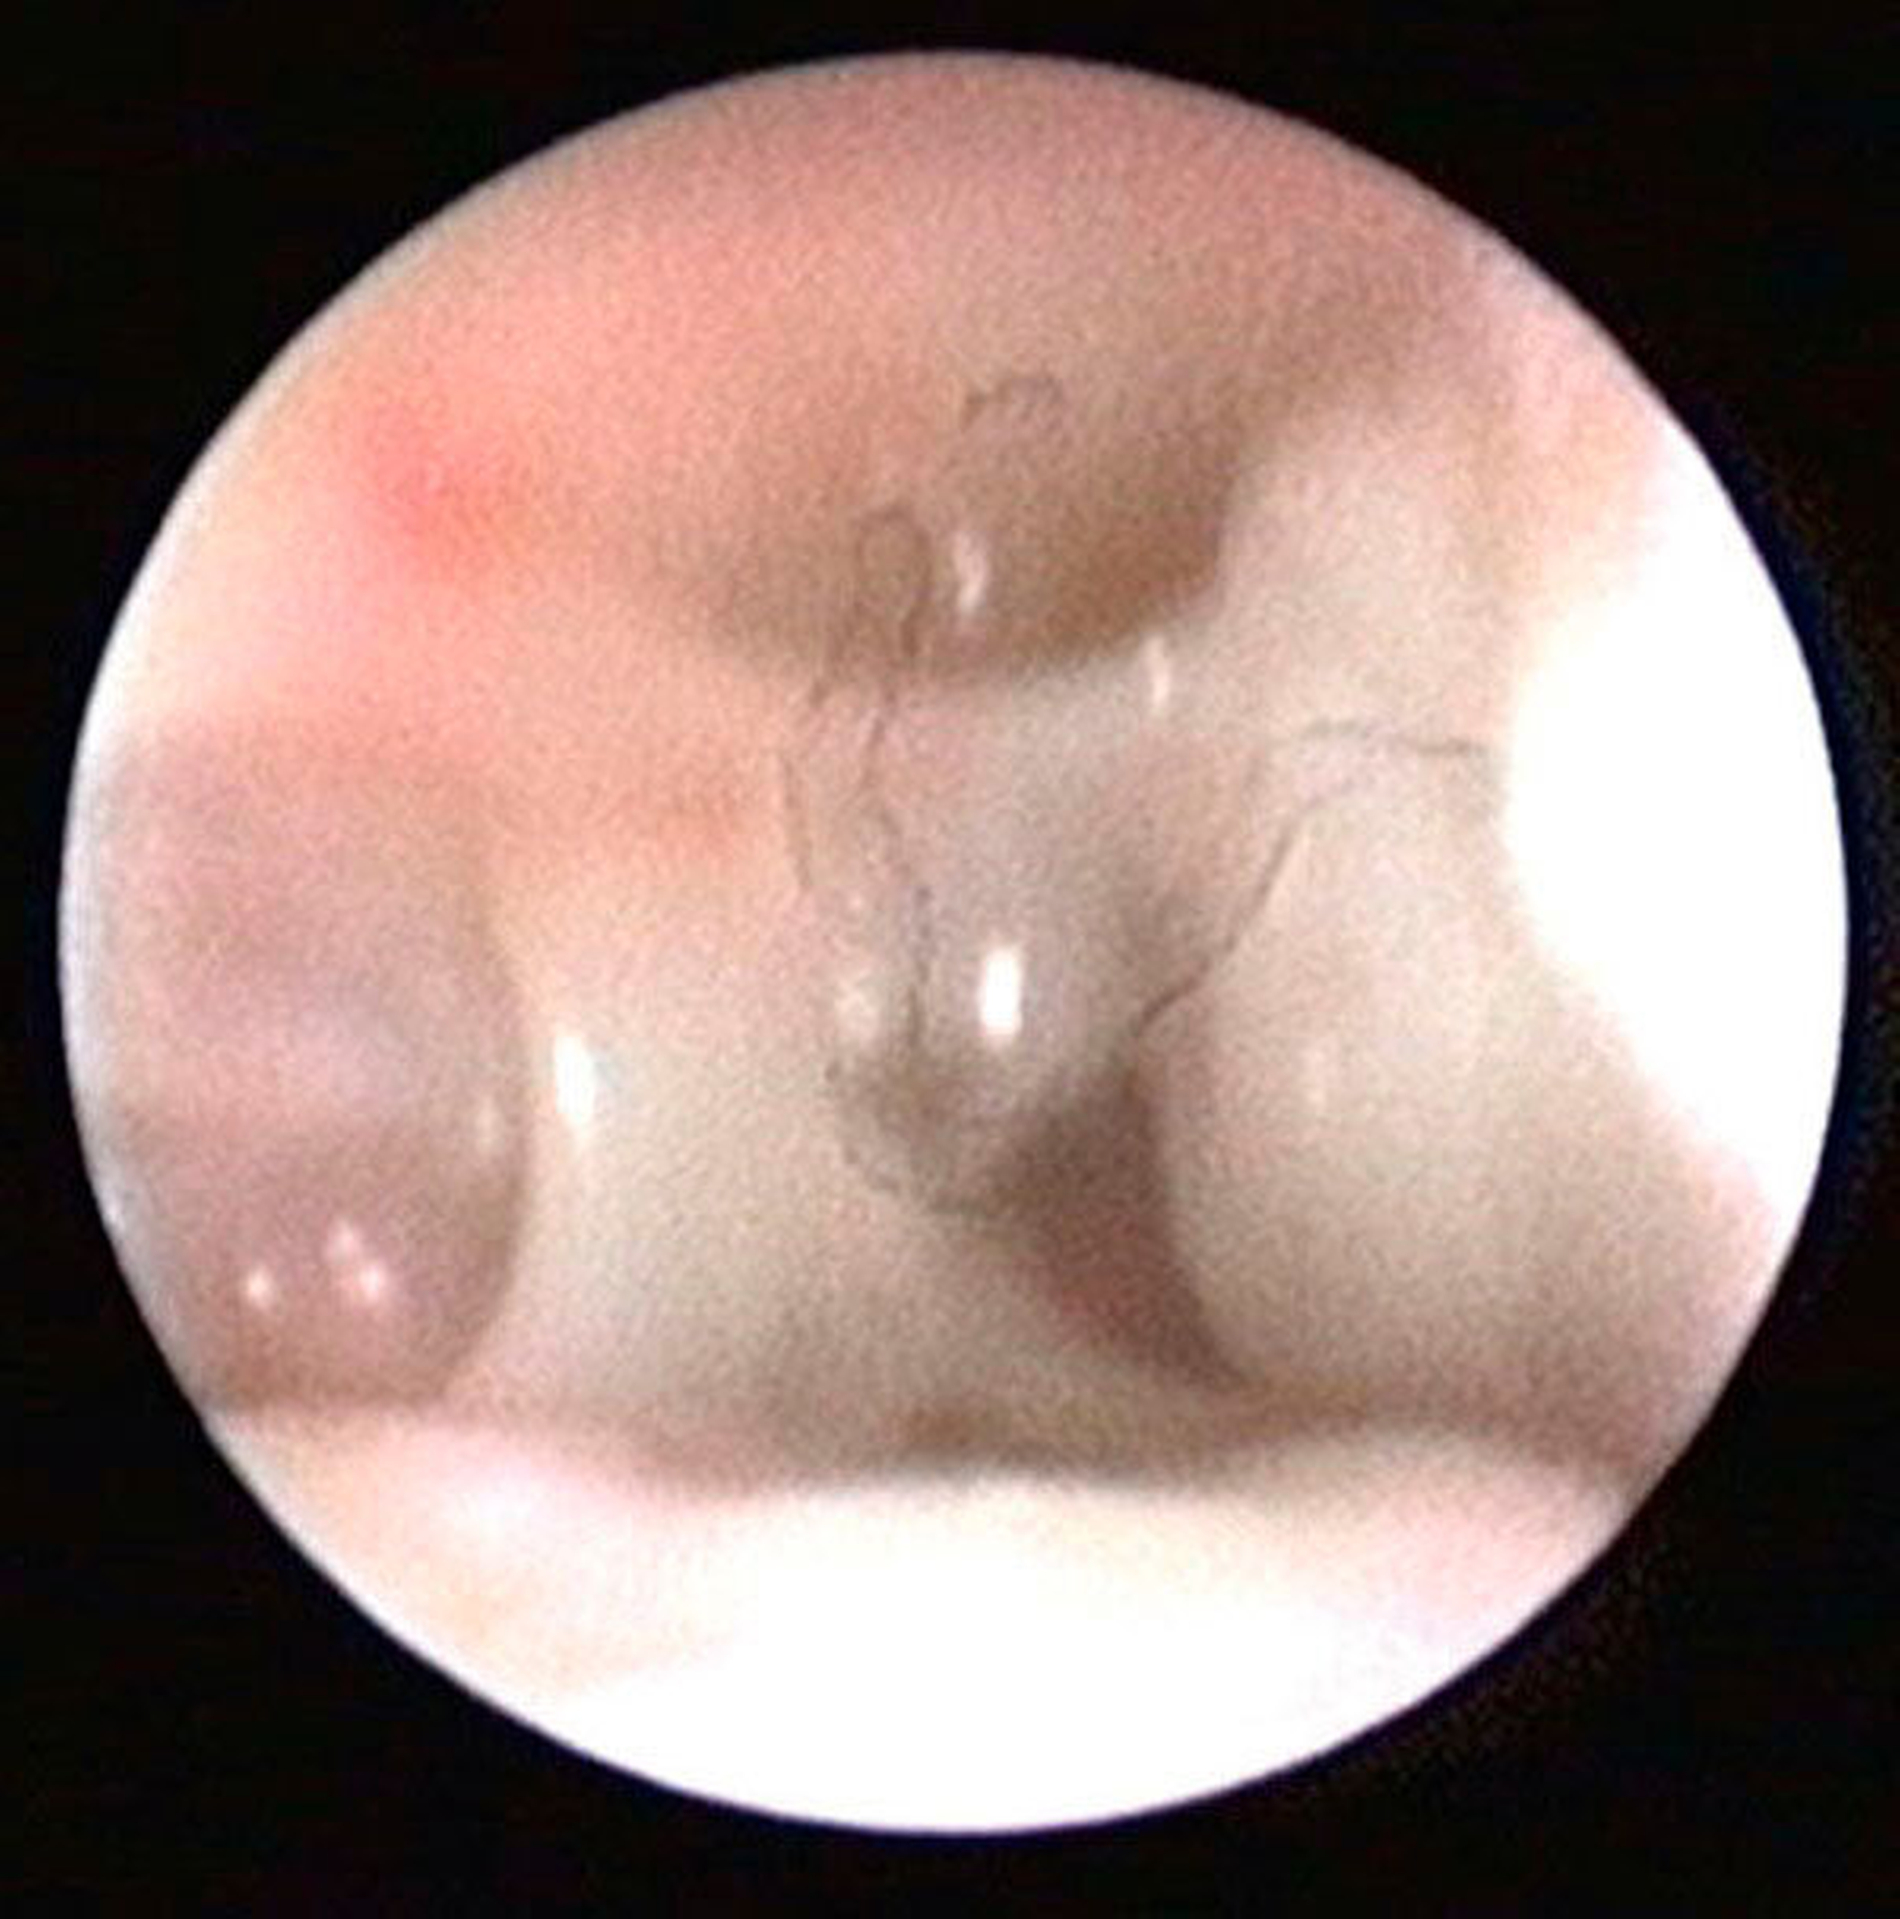

Die Kiefergelenksdestruktion wird als Ergebnis eines katabolen Prozesses verstanden, der die regenerativen Fähigkeiten des Gelenks überlagert und unter anderem durch eine kaskadenartige Aktivierung von Zytokinen vermittelt wird. Dabei kommt es neben einem Verstärkungseffekt durch die Synovial- und Gefäßproliferation zu einer Aktivierung von Osteoblasten. Zytokin-aktivierte Osteoblasten fördern die Rekrutierung und Aktivität von Osteoklasten, diese sezernieren wiederum Enzyme wie beispielsweise Matrix-Metalloproteasen (MMPs), die für den Abbau der extrazellulären Matrix (Hydroxylapatit und Kollagen) des Gelenks verantwortlich sind [Gunson et al., 2011; Zhang et al., 2016; Wang et al., 2012: Ge et al., 2011]. Die Schädigung des Gelenkknorpels wird dabei als „Chondromalazie“ bezeichnet und bei der arthroskopischen Diagnostik je nach Schweregrad im Stadium der Erweichung (Stadium 1), Furchung (Stadium 2), Fibrillation beziehungsweise Fransenbildung (Stadium 3) oder mit subchondraler Knochenexposition (Stadium 4) vorgefunden (Abbildungen 1 bis 3) [Quinn, 1989; Thomas et al., 1991].

Arthroskopisch existieren verschiedene Klassifikationen der Synoviitis, die im Wesentlichen das Ausmaß der beobachteten Gefäßproliferation und Hyperämie berücksichtigt (Abbildungen 4 bis 6) [Mc Cain et al., 1989; Gynther et al.,1994].

Zustände des „Internal derangements“ mit Blockaden gehören zu den Funktionsstörungen des Kiefergelenks und bedürfen in der Regel einer Abklärung dahingehend, wodurch die Mobilität des Diskus pathologisch reduziert ist. Infrage kommen hier beispielsweise die Diskusverlagerung ohne Reposition (Abbildung 7) oder das „Anchored Disc Phenomenon“. Bei Letzterem kommt die Gelenkblockade dadurch zustande, dass der Diskus nahezu unbeweglich in der Fossa verbleibt und die weitere Öffnungsbewegung behindert [Nitzan et al., 1997]. Neben Adhäsionen und Vernarbungen können im weiteren Verlauf auch schwerwiegendere degenerative strukturelle Schäden am Diskus auftreten, die oben genannten degenerativen Veränderungen können die Mobilität des Kiefergelenks dauerhaft einschränken (Abbildung 8). Bei Funktionseinschränkungen mit Blockaden kann die frühe Intervention durch eine therapeutische Arthroskopie einer Entstehung von Adhäsionen beziehungsweise Vernarbungen wirkungsvoll entgegenwirken (Abbildung 9), jedoch kann hier das Zeitfenster mitunter sehr klein sein [Zhang et al., 2011].

Die Kiefergelenksarthroskopie bietet bei gleichzeitiger Lavage eine überragende visuelle Diagnostik des oberen Gelenkraums (Abbildungen 1 bis 7, 13 und 14).

Im Fall diagnostizierter Pathologien können in der gleichen Sitzung arthroskopische therapeutische Maßnahmen durchgeführt werden (Abbildungen 8 und 9 ). Allerdings ist die Lernkurve der diagnostischen Arthroskopie im Vergleich zur Arthrozentese deutlich flacher, arthroskopisch-therapeutische Interventionen erfordern in der Regel eine zusätzliche Punktion für den Arbeitskanal und die Beherrschung der Triangulations-Technik. Weiterhin sind genaue Kenntnisse der arthroskopischen Anatomie und Pathologie des Kiefergelenks Voraussetzung.